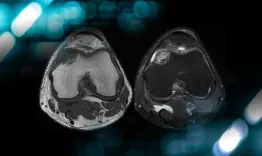

This video demonstrates a step-by-step, single-stage reconstruction of chronic PCL, PLC, and LCL injuries via minimally invasive approach.

Minimally invasive approach to multi-ligament knee reconstruction: arthroscopic PCL and PLC with percutaneous LCL reconstruction